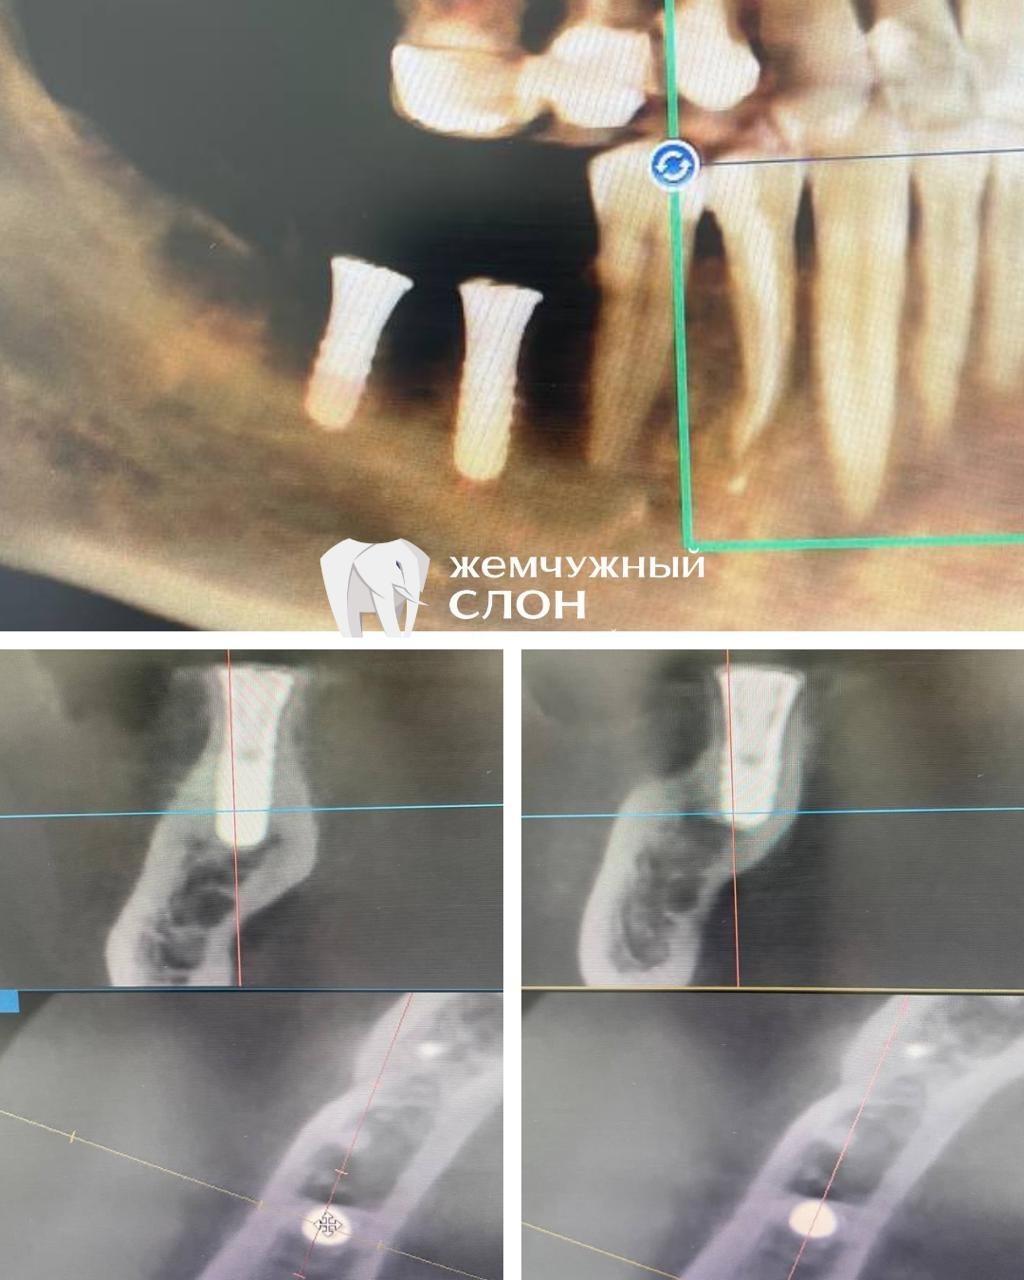

Имплантация Straumann без костной пластики

• Описание

Пациент обратился с недостаточным объемом костной ткани. Благодаря тщательному планированию по данным КЛКТ, хирург-имплантолог Хоботов Илья Дмитриевич установил два имплантата Straumann без необходимости костной пластики. Контрольный снимок подтвердил успешную остеоинтеграцию.

• Имплантолог

Хоботов Илья Дмитриевич

Установка двух имплантатов Straumann без костной пластики

У пациента был диагностирован дефицит костной ткани. Хирург-имплантолог Хоботов Илья Дмитриевич за один визит установил два имплантата Straumann без проведения костной пластики. Контрольная рентгенография подтвердила стабильную остеоинтеграцию, позволив пациенту быстрее перейти к протезированию.